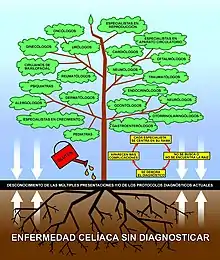

A fecha de 2019, se calcula que la mayoría de los celiacos en la mayoría de los países del mundo nunca llega a recibir un diagnóstico.[65] Esto es debido al escaso conocimiento sobre la celiaquía existente entre los profesionales de la salud, incluyendo médicos de cabecera, pediatras, gastroenterólogos y especialistas en general,[65][17][12][66] y a las dificultades del diagnóstico.[65][27][41][67] Cinco de cada seis celíacos (aproximadamente el 83 %) permanece sin diagnosticar.[42] En los niños, las cifras llegan a alcanzar el 90 %.[68] En aquellos que consiguen ser diagnosticados, el tiempo transcurrido desde el comienzo de los síntomas es habitualmente muy prolongado, con retrasos diagnósticos que pueden oscilar entre los siete y los cincuenta y nueve años,[69] período durante el que los pacientes acuden a repetidas consultas de diversos especialistas, los cuales por lo general, no piensan que la celiaquía pueda ser la enfermedad que causa sus diversas molestias.[70][71][72][73] No existe ninguna prueba que por sí sola pueda descartar la enfermedad celíaca.[27][74] Una gran parte de celiacos son diagnosticados por error como sensibilidad al gluten no celíaca.[40]

El retraso medio en la celiaquía entre el comienzo de los síntomas y el momento del diagnóstico es habitualmente muy prolongado, con una media de unos diez años en la mayor parte de los casos, con límites amplios que pueden oscilar entre los 7 y los 59 años,[69] período durante el cual los pacientes acuden a repetidas consultas de diversos especialistas, los cuales por lo general, no piensan que la celiaquía pueda ser la enfermedad que causa sus diversas molestias.[70] [71] [72] [73]

La media estimada de tiempo que transcurre desde el comienzo de aparición de los síntomas hasta que el paciente consigue el diagnóstico, es de unos 20 años. Esta situación se puede explicar teniendo en cuenta que, a pesar de los avances realizados en los últimos años en la identificación de las múltiples manifestaciones de la enfermedad celíaca y a la reforma de los protocolos diagnósticos, estos conocimientos aún no han llegado a la mayoría de profesionales a los que acude a consultar el paciente por molestias variadas y diversas que presenta.

Se necesita una mayor conciencia de la celiaquía como un problema de salud común. Acortar el retardo diagnóstico, actualmente muy elevado, es imprescindible para reducir la carga innecesaria de la enfermedad. Vivir con una enfermedad celíaca sin diagnosticar incrementa el riesgo de consecuencias negativas sobre la salud y la mortalidad.[73] [165] [166] [167] [168] [169] [170] La correcta identificación y tratamiento con la dieta sin gluten (DSG) prevendrá de las numerosas complicaciones digestivas y extra-digestivas que pueden aparecer a corto, medio o largo plazo, entre las que cabe destacar especialmente enfermedades por carencias crónicas, procesos de naturaleza inmuno-alérgica, diferentes procesos autoinmunitarios, diversos tipos de cánceres, enfermedades cardiovasculares, trastornos neurológicos y psiquiátricos.[19][29][45][171] [172] [173] [174] [175]

Los errores más frecuentes radican en la dificultad de la identificación y diagnóstico de la enfermedad celíaca ante presentaciones no clásicas, que son las más frecuentes, en las que la afectación digestiva es menor y/o intermitente y abundan las manifestaciones extra-digestivas, con serología negativa (ausencia de anticuerpos en sangre) y con biopsias duodenales que presentan cambios mínimos, sin atrofia vellositaria (Marsh 1).[177]